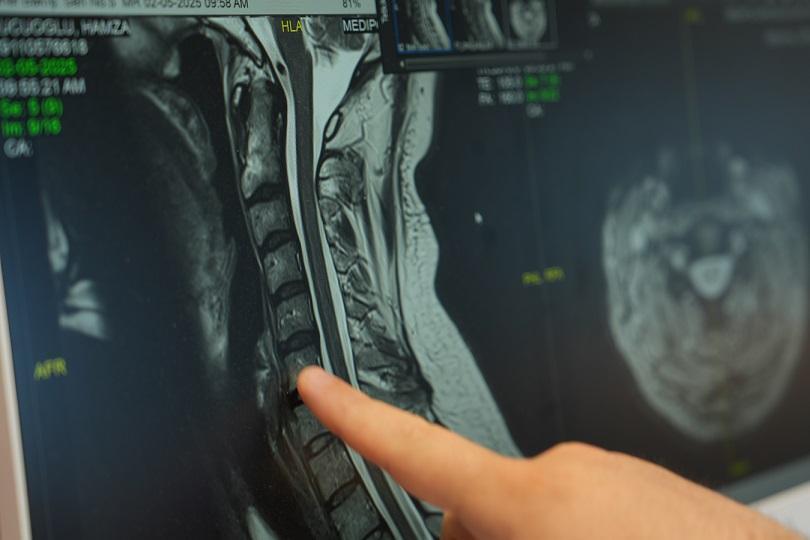

Özellikle cep telefonu, tablet ve bilgisayar gibi teknolojik cihazların kullanım süresinin artmasının hastalığın görülme sıklığını artırdığını söyleyen Doç. Dr. Sucuoğlu, “Başın normal duruş pozisyonunda boyuna binen yük 4-5 kilo iken, öne eğik pozisyonda bu yük 25-30 kiloya kadar çıkabiliyor. Bu durum, omurlar arasındaki disklerin yapısını bozarak fıtıklara yol açabiliyor” dedi.

Cep boyun hastalığının önlenmesinde ailelerin ve öğretmenlerin rolüne vurgu yapan Doç. Dr. Sucuoğlu, “Aileler, çocuklarının teknoloji kullanımlarını denetlemeli ve süreyi sınırlamalıdır. Okullarda da öğretmenler, öğrencilere doğru oturma ve cihaz kullanma alışkanlıklarını kazandırmalıdır” dedi. Cep boyun hastalığının tedavi edilmediği takdirde boyun fıtıkları, omurga eğrilikleri ve postür bozukluklarına yol açabileceğini belirten Doç. Dr. Sucuoğlu, “Bu hastalık sadece boyun ağrısı ile sınırlı kalmayıp kamburluk, boyun düzleşmesi ve omurga deformitelerine neden olabiliyor. Bu nedenle erken müdahale büyük önem taşıyor” diye konuştu.